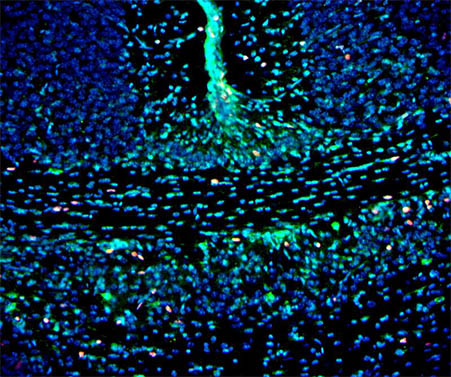

荧光显微镜用于小鼠荧光脑片观察

脑科学,是为了了解神经系统内分子水平、细胞水平、细胞间的变化过程,以及这些过程在控制系统内的整合作用而进行的研究。本次实验选用明美荧光显微镜来观察小鼠荧光脑片,做进一步研究。

深圳区域工程师给老师推荐了明美荧光显微镜MF43-N,采用优良的无限远光学系统,6孔转盘式荧光模块设计,荧光更换拆除方便,可自主方便更换想要的荧光激发块,“一机多色”从此不是梦。

荧光可根据不同染料波段选择不同的荧光激发块,信噪比高,应用面广,可以扩展应用在FISH领域、FRET领域、CTC检测领域。